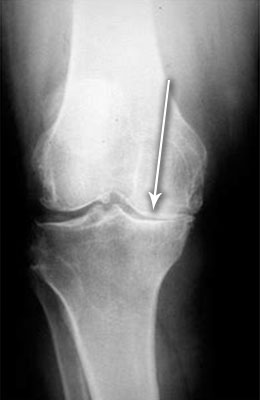

Uitați-vă la aceste imagini, puteți vedea că în imaginea din dreapta nu există spațiu articular, oasele se freacă unele de altele, provocând dureri puternice. Iar acest proces este foarte greu de oprit! În câțiva ani, persoana va deveni invalidă și nu va mai fi capabilă să aibă grijă de sine.